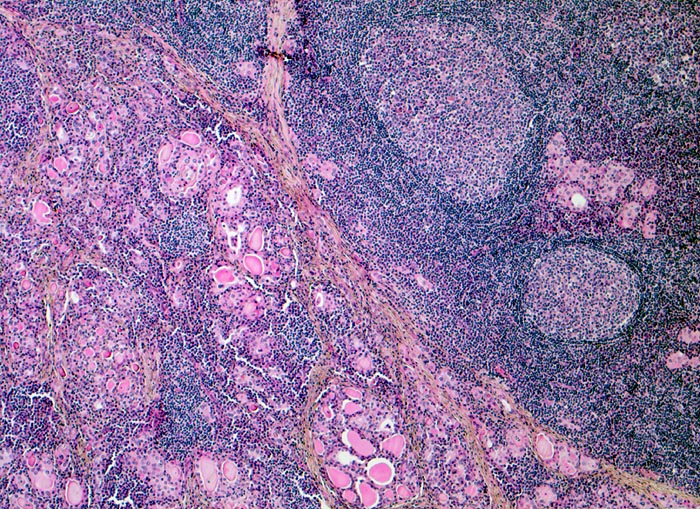

chronische lymphozytäre Thyreoiditis Hashimoto

Schilddrüse

Mikrofollikuläres Schilddrüsenparenchym mit wenig Kolloid. Das Parenchym wird infiltriert und partiell zerstört durch ein dichtes lymphoides Entzündungsinfiltrat mit sekundären Lymphfollikeln. Stellenweise sind nur kleine Epithelinseln im Entzündungsinfiltrat stehengeblieben.

Die Patientin sucht den Hausarzt auf wegen leichter Schmerzen am Hals rechts. Symptome einer Schilddrüsendysfunktion sind auch auf gezielte Anfrage hin nicht vorhanden. Die Schilddrüse ist deutlich vergrössert. Die laborchemischen Untersuchungen ergeben eine pathologisch erhöhte Konzentration der Peroxidase- und Thyreoglobulin-Antikörper. Die Serumwerte für T4 und T3 sind normal, der Wert für TSH ist erhöht. Die Indikation zur Thyreoidektomie wird wegen der deutlichen Struma gestellt.